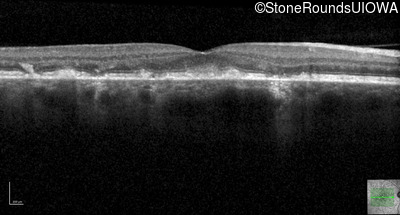

Optical Coherence Tomography - Left - 20/32 sc

Exemplar / OCT Stack